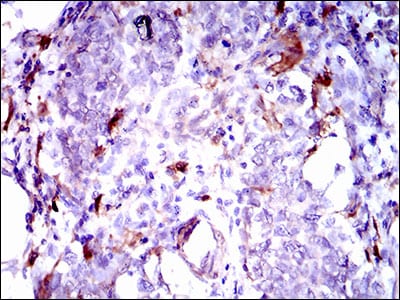

分类: 科研抗体货号: 30511别名: CASH; FLIP; MRIT; CLARP; FLAME; Casper; FLAME1; c-FLIP; FLAME-1; I-FLICE; c-FLIPL; c-FLIPR; c-FLIPS; CASP8AP1应用: WB,IHC,FCM反应种属: Human,Mouse